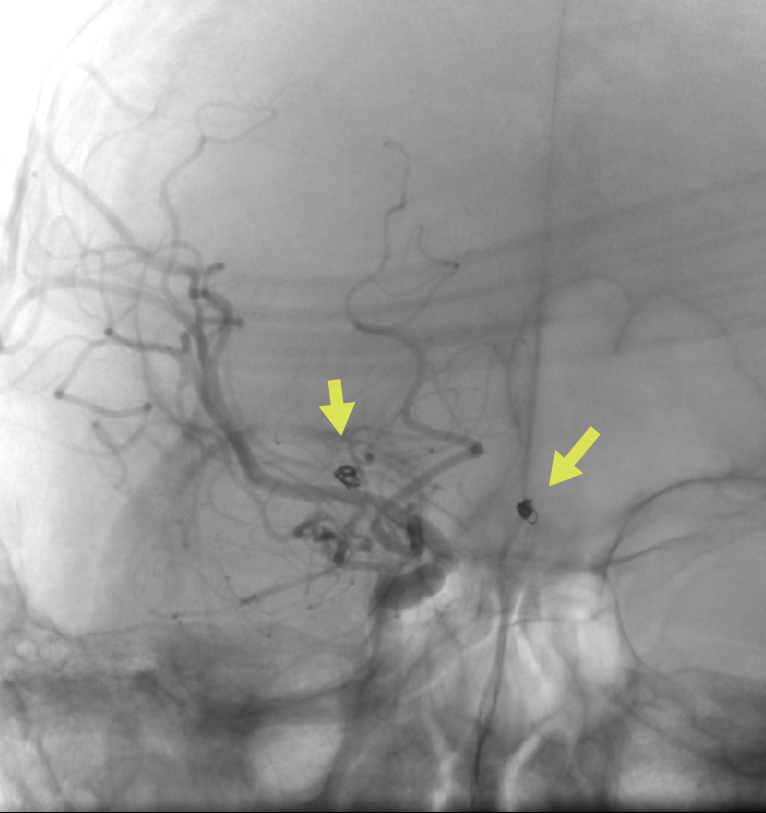

CTA檢查(箭頭為動脈瘤)

經(jīng)過充分評估,惠州三院神經(jīng)醫(yī)學(xué)中心李雪松博士神經(jīng)介入治療團隊在導(dǎo)管室、麻醉科等科室密切配合下,通過右側(cè)股動脈進行穿刺,先進行全腦血管造影(DSA)檢查。2個動脈瘤分別顯現(xiàn),右側(cè)大腦中動脈1個,前交通動脈上還有1個,兩個動脈瘤中任何一個都可能破裂。

經(jīng)過2個小時的努力,神經(jīng)介入治療團隊通過一次手術(shù)將2個動脈瘤用彈簧圈填塞處理,成功完成栓塞,將顱內(nèi)的“兩彈”順利拆除。手術(shù)后孫先生很快麻醉蘇醒,經(jīng)過醫(yī)生的對癥治療后頭痛等癥狀消失,感覺好多了。

動脈瘤栓塞術(shù)后血管造影